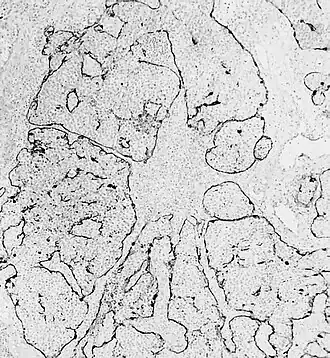

Esthésioneuroblastome.

L'esthésioneuroblastome (ou neuroblastome) olfactif est une tumeur rare se développant aux dépens du nerf olfactif dans la cavité nasale. Moins de 1 000 cas dans le monde ont été publiés durant les vingt dernières années[1]. Les causes de cette tumeur restent inconnues. La pathologie a été décrite pour la première fois dans la littérature par Berger et Luc en 1924[2].